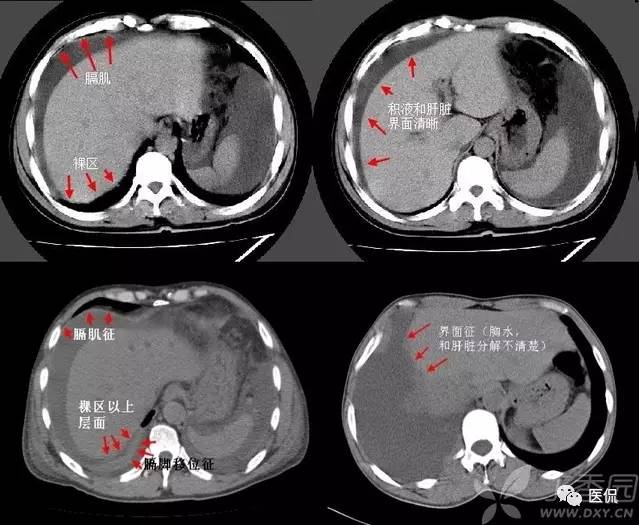

胸腹水鉴别四联症

1、膈肌征:横隔顶向头侧凸出,低密度影在膈外周为胸水,在膈内为腹水。

2、膈脚移位征:胸水时压迫膈脚向前、向外侧移位。

3、界面征:肝与肺在层面上的分界一般是清晰的,腹水时也清晰明确,而当胸水时则肝肺分界不清晰。

4、肝裸区征:肝的背侧内部肝与膈肌直接相贴,此为裸区,产生腹水时液体不在此区潴留。